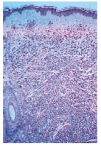

El estudio histológico de las lesiones, tanto de los nódulos como de las maculopápulas, ponía de manifiesto la existencia, bajo una epidermis normal, de un denso infiltrado que ocupaba desde dermis media hasta hipodermis respetando una fina banda superficial (fig. 3). El infiltrado era monomorfo y estaba formado por células de citoplasma escaso y núcleos irregulares con abundantes mitosis (fig. 4). En el estudio inmunohistoquímico se evidenciaba que dichas células pertenecían a la serie monocito-histiocitaria (CD43+, CD68+, CD15+) (fig. 5), con índice proliferativo muy alto (fig. 6).

Fig. 3.--Tinción con hematoxilina-eosina. Epidermis sin alteraciones. Denso infiltrado desde dermis media, respetando una banda superficial.